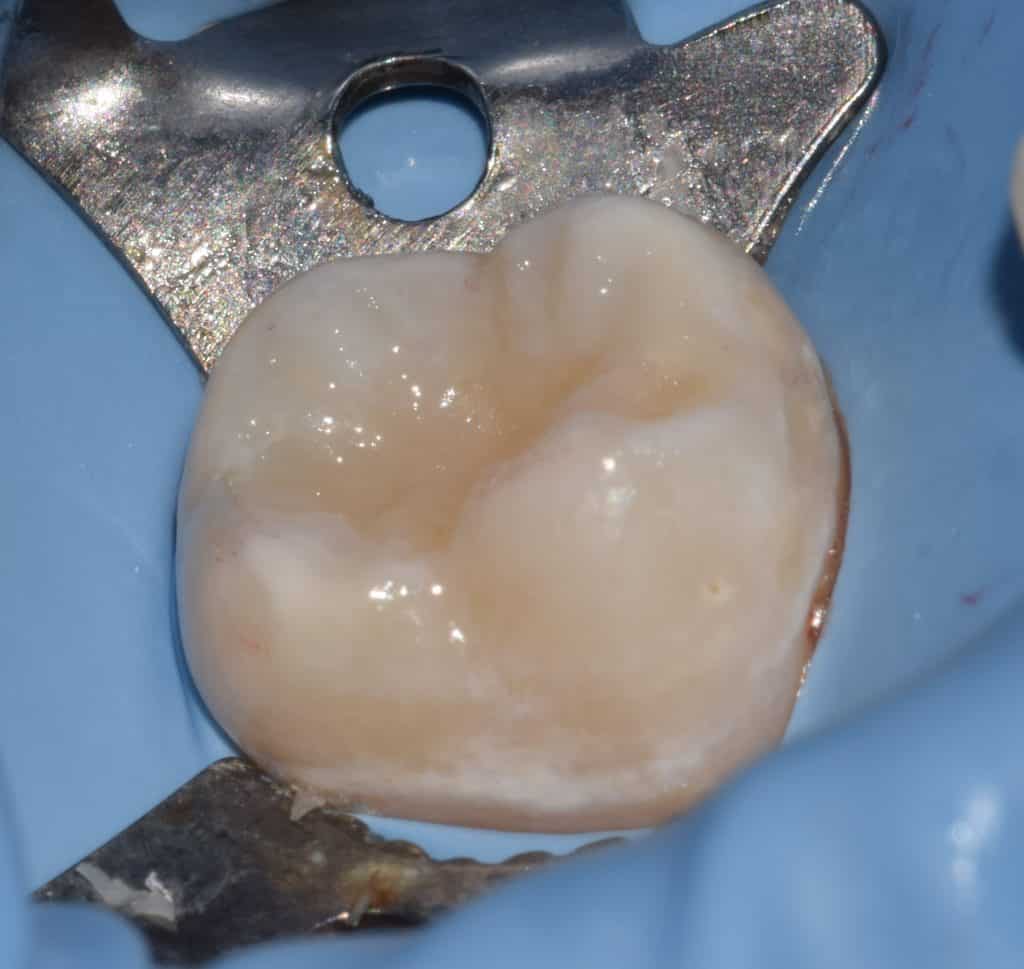

First the liquid dam was dispensed over the occlusal surface by syringe and the burnisher inserted inside the material, then the light was applicated for polymerization of material.

Hard instrument that have resistance to deformation during application and removal of occlusal print.

Have a good retentive bull end for holding the liquid dam.